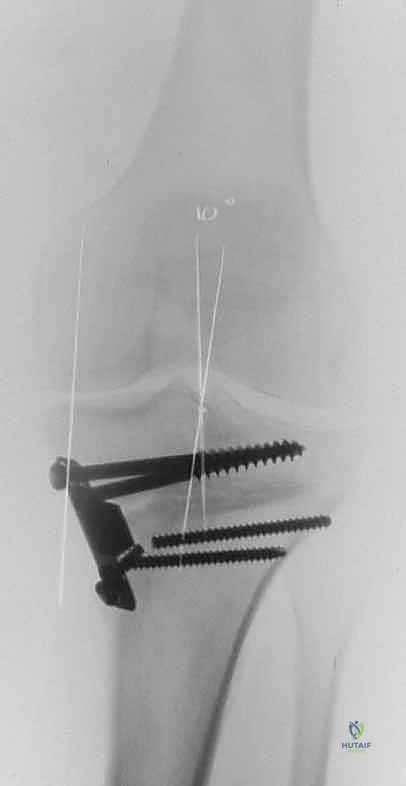

A C B D TECH FIG 7•A.

B.

Intraoperative final AP radiograph.

C,D.

Postoperative AP and lateral radiographs.